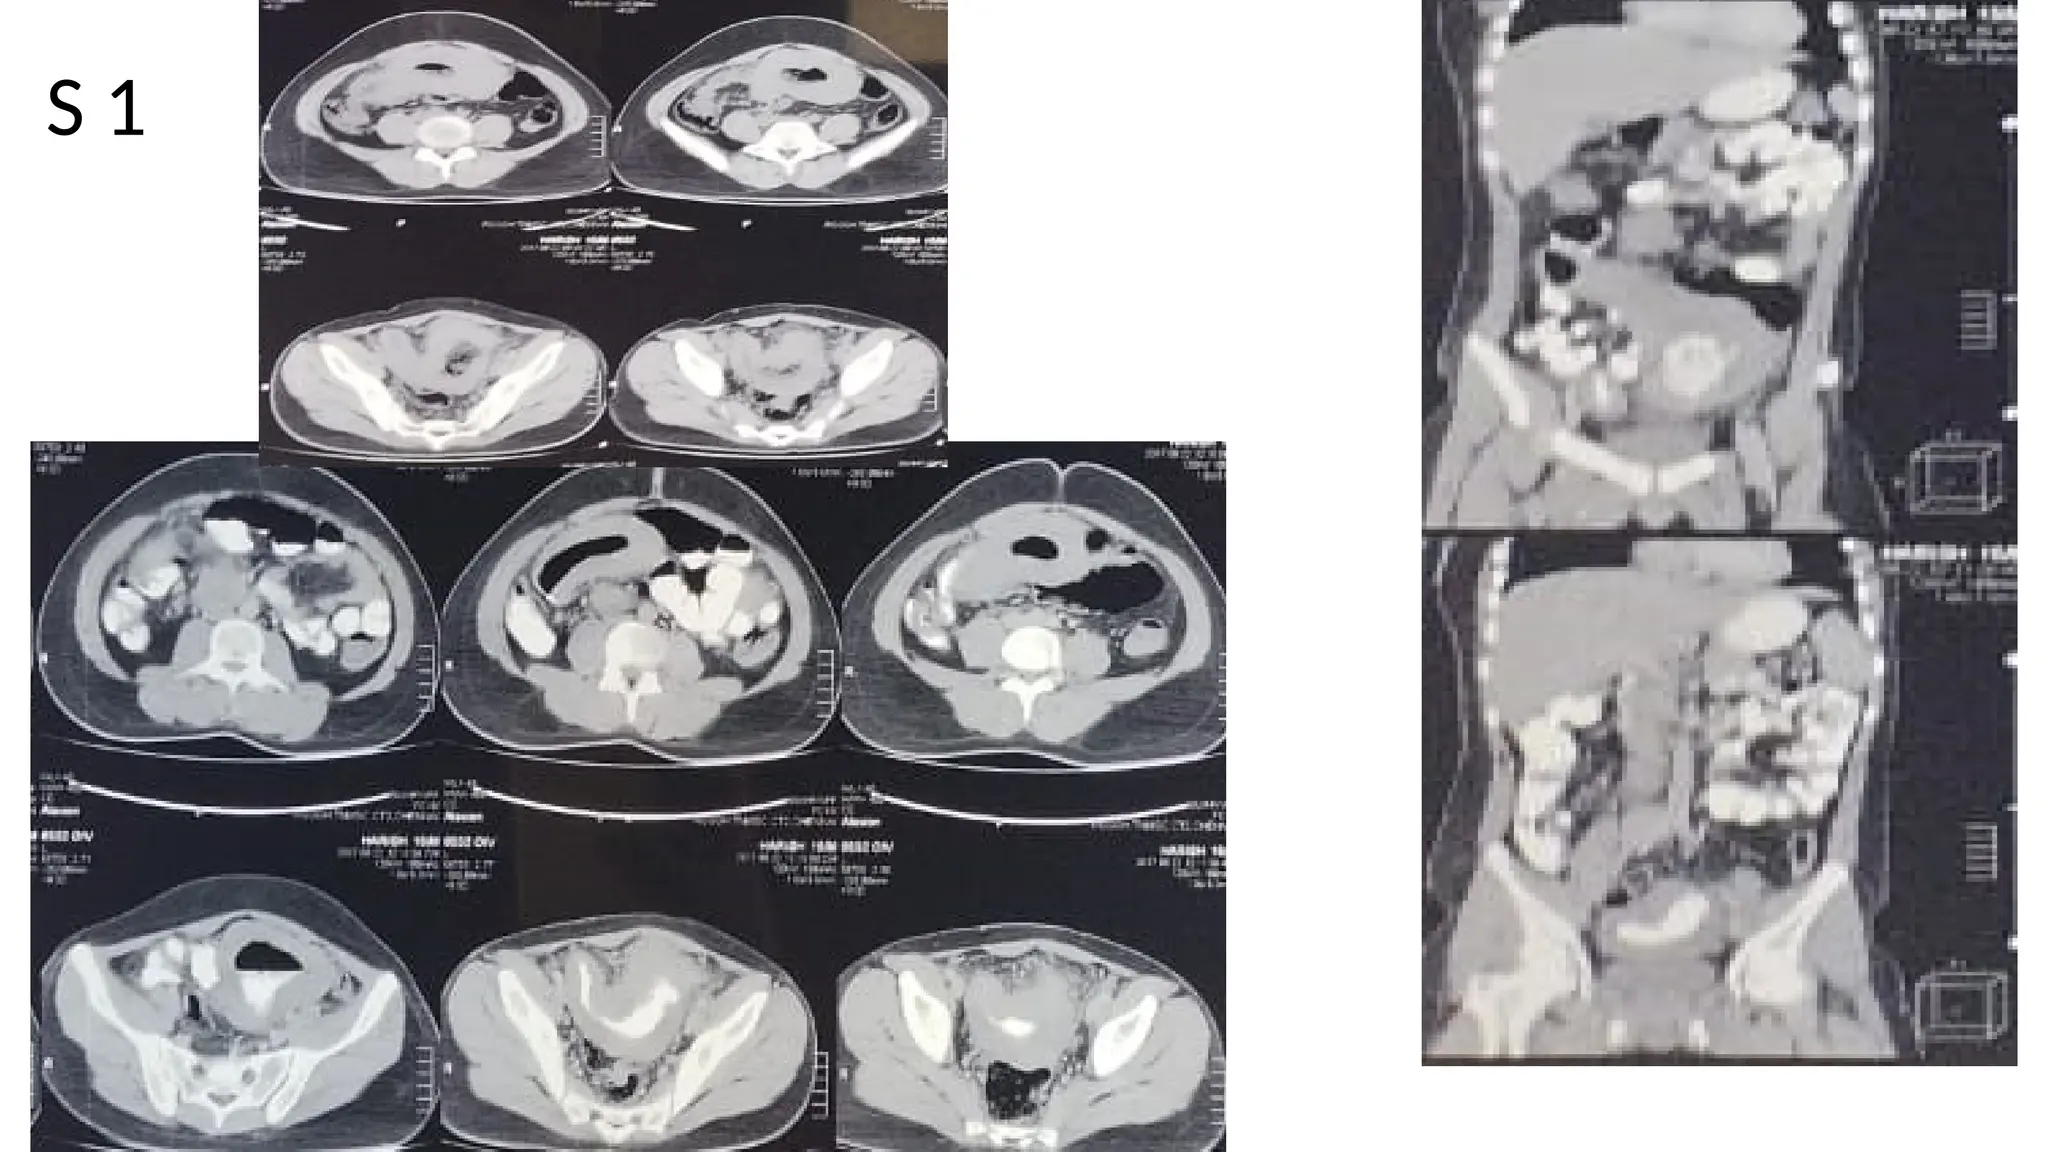

The document lists various components and classifications related to the gastro-intestinal system. It includes multiple codes and identifiers associated with different aspects of this biological system. The content appears to be a structured categorization rather than a narrative or descriptive text.